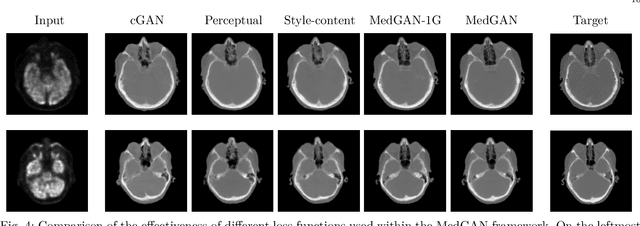

Abstract:Image-to-image translation is considered a next frontier in the field of medical image analysis, with numerous potential applications. However, recent advances in this field offer individualized solutions by utilizing specialized architectures which are task specific or by suffering from limited capacities and thus requiring refinement through non end-to-end training. In this paper, we propose a novel general purpose framework for medical image-to-image translation, titled MedGAN, which operates in an end-to-end manner on the image level. MedGAN builds upon recent advances in the field of generative adversarial networks(GANs) by combining the adversarial framework with a unique combination of non-adversarial losses which captures the high and low frequency components of the desired target modality. Namely, we utilize a discriminator network as a trainable feature extractor which penalizes the discrepancy between the translated medical images and the desired modalities in the pixel and perceptual sense. Moreover, style-transfer losses are utilized to match the textures and fine-structures of the desired target images to the outputs. Additionally, we present a novel generator architecture, titled CasNet, which enhances the sharpness of the translated medical outputs through progressive refinement via encoder decoder pairs. To demonstrate the effectiveness of our approach, we apply MedGAN on three novel and challenging applications: PET-CT translation, correction of MR motion artefacts and PET image denoising. Qualitative and quantitative comparisons with state-of-the-art techniques have emphasized the superior performance of the proposed framework. MedGAN can be directly applied as a general framework for future medical translation tasks.